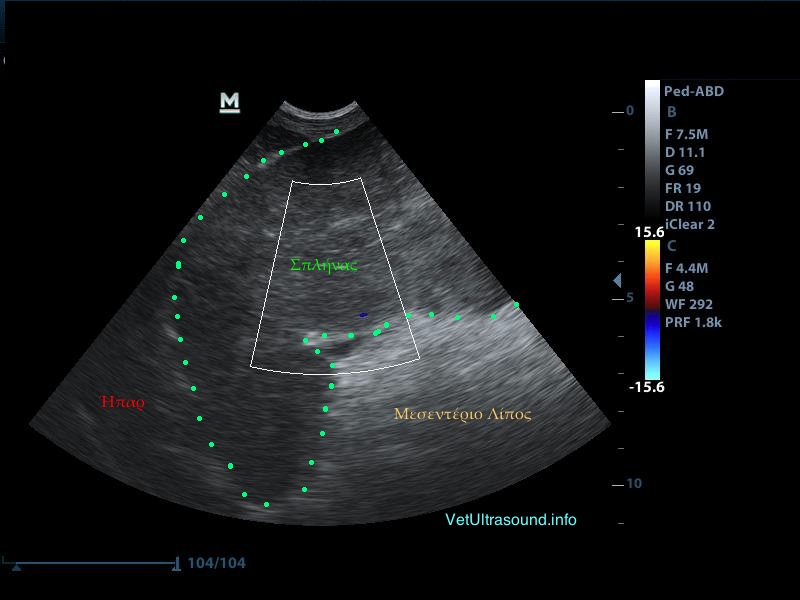

Διάγνωση: Ο σπλήνας ελέγχθηκε διογκωμένος και διάχυτα υποηχογενής χωρίς εστιακές αλλοιώσεις στο παρέγχυμά του. Το μεσεντέριο λίπος γύρω από αυτόν ήταν αρκετά υπερηχογενές και βρέθηκε μικρή παρουσία ασκιτικού υγρού ανάμεσα από τις εντερικές έλικες. Το έγχρωμο Doppler δεν έδειχνε αιμάτωση του σπλήνα και ιδιαίτερα των μεγάλων αγγείων. Η διάγνωση τέθηκε ως συστροφή σπλήνα και ο ασθενής οδηγήθηκε στο χειρουργείο.

– Το υπερηχογενές λίπος στην προκειμένη περίπτωση οφείλεται στην συστροφή των αγγείων και του λίπους με τη σειρά του στη πύλη του σπλήνα.

– Ο σπλήνας εμφανίζεται έτσι λόγω του οιδήματος που δημιουργείται από την παθητική συμφόρηση εξαιτίας του στραγγαλισμού των αρτηριών και των φλεβών που των αιματώνουν.